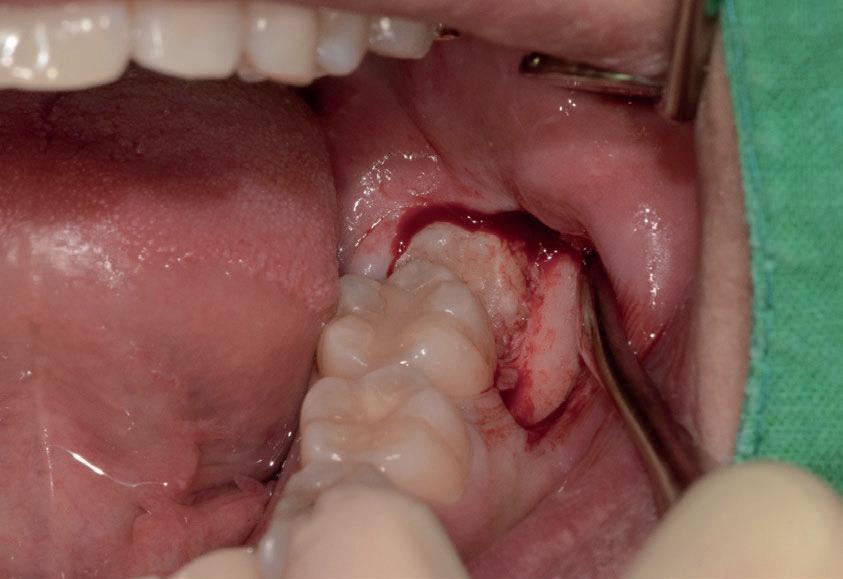

Il seguente caso chirurgico è di un 4.8 mesio-inclinato e parzialmente incluso. Dopo un’incisione a busta, il

dente è stato separato al centro per fare una coronectomia, prima della porzione distale e successivamente della porzione mesiale. Facendo leva quindi è stato possibile rimuovere le radici unite. Figg. 165-172

Figg. 165-172 - Caso 3: tecnica di estrazione con divisione orizzontale utilizzando il manipolo dritto. Fig. 165 Fig. 166 Fig. 167 Fig. 168 Fig. 169 Fig. 170 Fig. 171 Fig. 172